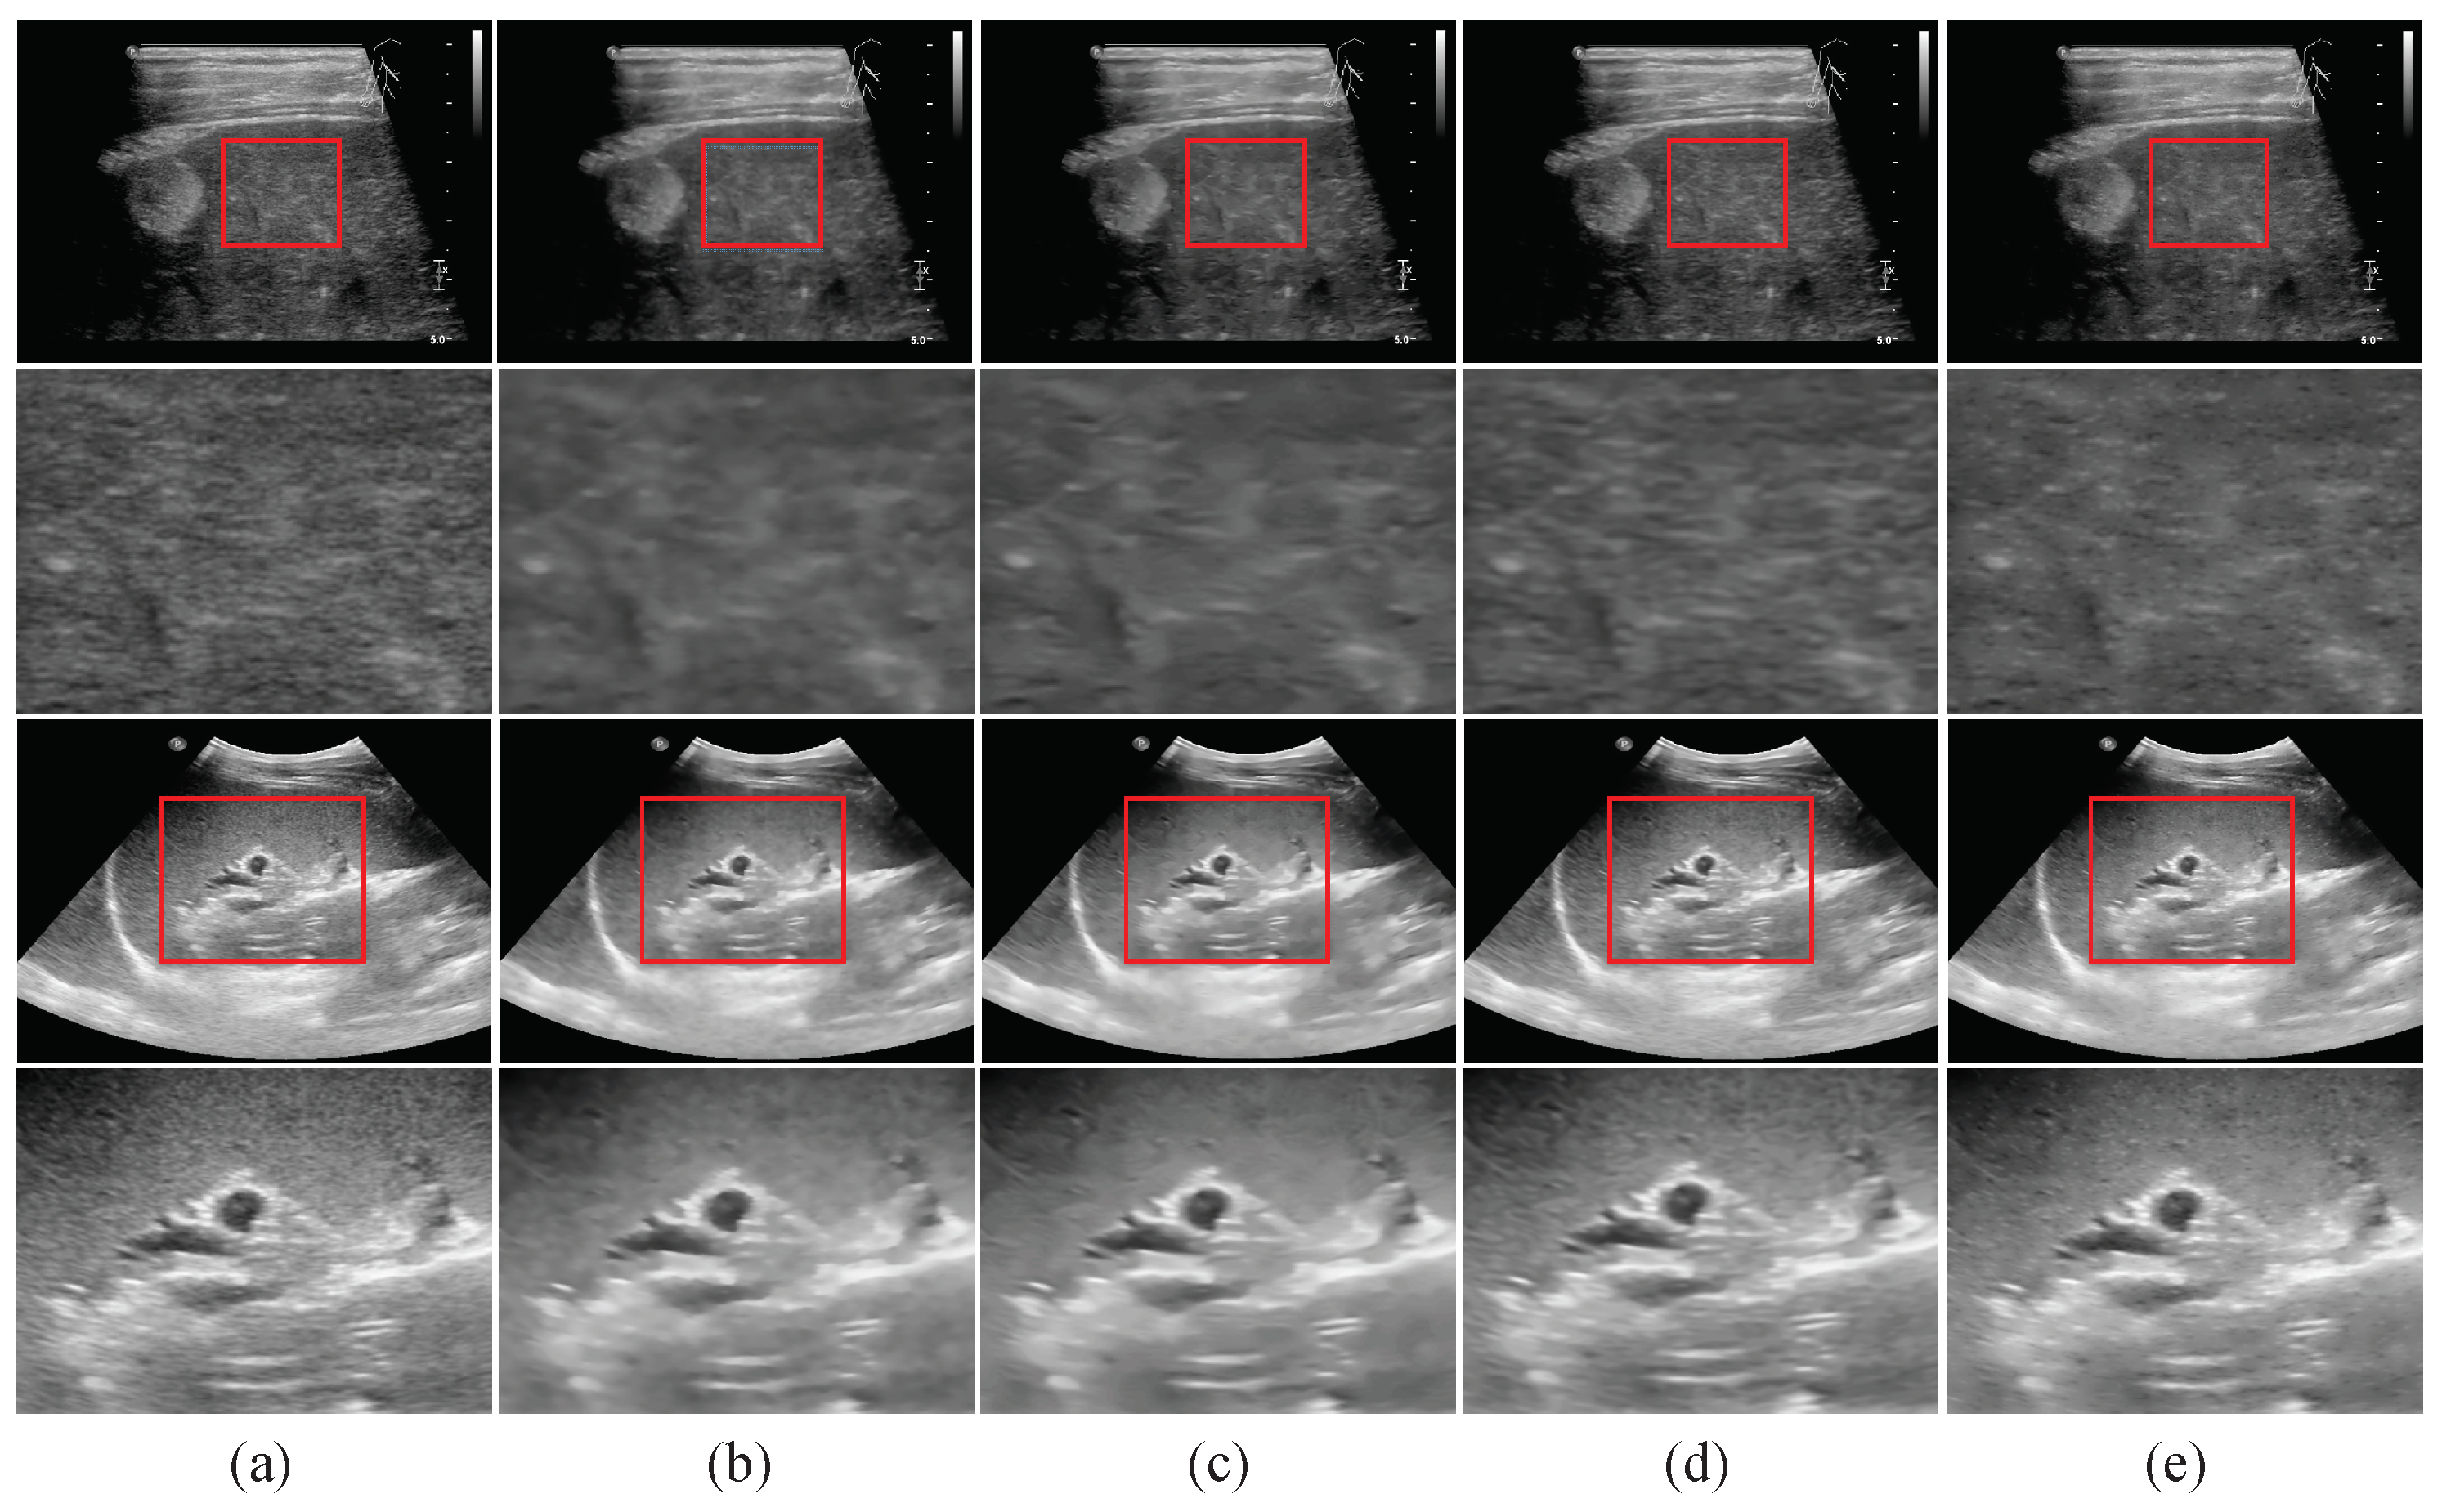

3.3. Tests on Real Ultrasound Images